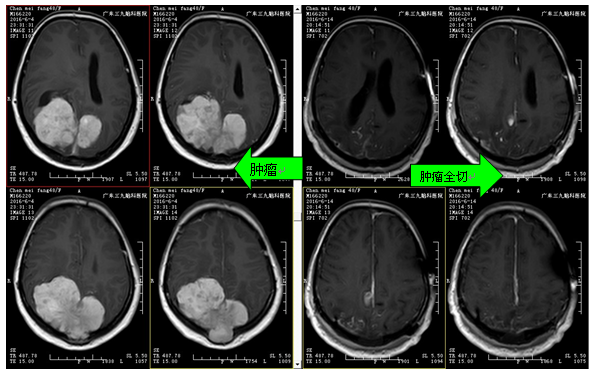

陈女士,28岁,于2年前无明显诱因出现头痛,偶有呕吐;半年前因出现动作迟缓、行走不稳;上述症状呈进行性加重,当地医院行头颅CT平扫提示双侧枕顶巨大肿瘤,今为进一步诊治来我院就诊。诊断:双侧枕顶部镰窦旁巨大脑膜瘤

治疗:入院后予完善相关检查,先行“肿瘤供血血管介入栓塞术”,术后在全麻下行右枕顶部占位性病变切除术,最后全切肿瘤。术中出血约1400ml,输血约1000ml。经治疗,患者目前无头晕、头痛,无恶心、呕吐等不适,肌张力正常,右下肢肌力3级,生理反射存在,病理征阴性。

广东三九脑科医院神经外二科林涛主任点评:该患者为双侧枕顶部肿瘤,肿瘤体积巨大,侵犯后矢状窦、窦汇、横窦,同时侵犯相应硬脑膜,部分肿瘤组织突破颅骨进入皮下,肿瘤侵犯大脑镰往左侧生长,其血管极其丰富,颈内及颈外大血管均参与供血,血管造影见肿瘤染色明显,因此预计手术难度及风险性均较高。我科经研究决定先采取介入栓塞手术段,将肿瘤主要供血血管进行栓塞,从而大大减少术中出血,接着再行肿瘤切除。该手术运用导航定位、电生理监测、超声吸引、术中超声、钨刀等先进技术设备,准确定位肿瘤范围,步步为营,逐步分离并分块全切除肿瘤。经近12小时“浴血奋战”,成功切除了肿瘤,而且到目前术后并发症(语言功能障碍、肢体运动功能障碍、迟发血肿、再灌注损伤、癫痫等)未发现,头痛症状明显改善。